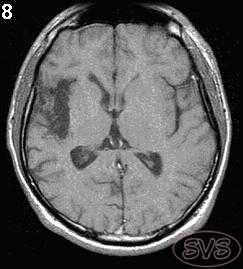

Ранние дегенеративные изменения в мозге возникающие в период беременности, пери- или постнатально проявляются виде порэнцефалии, энцефаломаляции и т.д., что достаточно хорошо выявляется с помощью МРТ. Посттравматические рубцово-атрофические изменения у взрослых часто могут сопровождаться эпилепсией (рис 8).

Рис 8. Посттравматические рубцово-атрофические изменения в правой височной доле с энцефаломаляцией (Т1-взв. изображение).